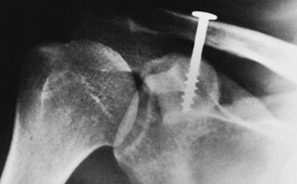

Figure 15.8.

Anteroposterior radiograph illustrating a type C glenoid neck fracture. This is not a complete fracture of the glenoid neck because the superior portion of the glenoid remains intact. |